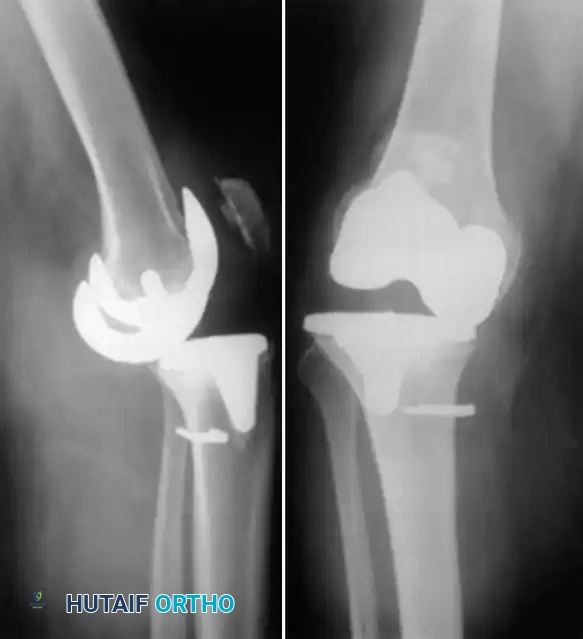

Fig. 6-69 A and B, LISS plate fixation of periprosthetic femoral fracture.

For supracondylar femoral fractures above a TKA, if the prosthesis remains stable, open reduction and internal fixation (ORIF) using locked plating (e.g., LISS plate) or intramedullary nailing is indicated. If the prosthesis is unstable, a stemmed revision TKA, often requiring distal femoral allografts or tumor mega-prostheses, is mandatory.

Fig. 6-71 Anatomical locations of tibial fractures associated with total knee arthroplasty.

Tibial periprosthetic fractures (Felix classification) are similarly managed based on the anatomical location of the fracture relative to the stem, the stability of the implant, and the timing of the fracture (intraoperative vs. postoperative).

Fig. 6-72 Lucency at the entire bone-cement interface of the tibial component, with deformity and subsidence of the component.

Incomplete radiolucencies of less than 2 mm are common and do not necessarily correlate with poor clinical outcomes. However, radiolucent lines around uncemented implants indicate regions where osteointegration has failed. If these lines are extensive, progressive, or symptomatic, aseptic loosening is highly probable.

Fig. 6-73 Loose uncemented femoral component with subsidence into an extended position relative to the distal femur.

Surgical Warning: A radiolucent line under a metal-backed tibial component can be easily obscured by as little as 4 degrees of knee flexion. Fluoroscopic examination is highly recommended for patients with unexplained pain and seemingly "normal" static radiographs. Fluoroscopy allows the x-ray beam to be positioned perfectly parallel to the implant surfaces, unmasking subtle radiolucencies.